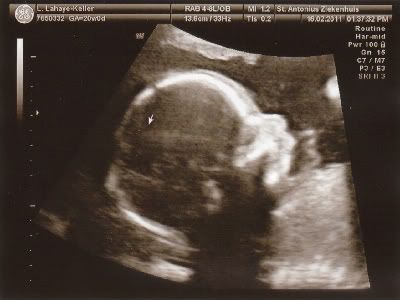

We hebben vandaag de 20 weken echo gehad en alles is in orde met de kleine!

Moet nog wel een keer terug volgende week, want ze kon niet alles goed zien maar de belangrijkste dingen waren helemaal in orde! Ben echt opgelucht... Hieronder wat echo foto's.

Lijkt me duidelijk wat het wordt hahahahaha.....!!!

Voor degene die niet zo goed in echo's zijn......